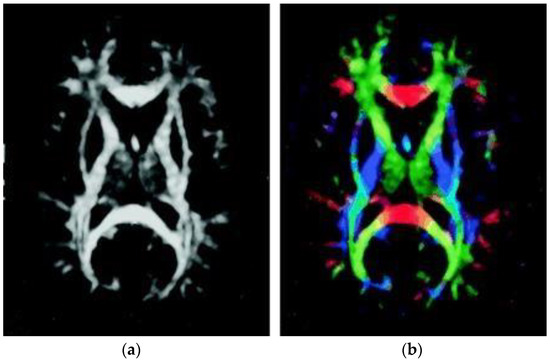

2.3. Diffusion Tensor Images Preprocessing

2.4. TBSS and Structural Parcellation